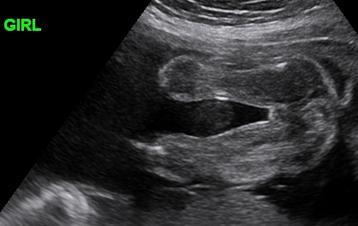

What It Would Look Like. A regular 2-D ultrasound creates a cross-sectional view of your baby. Did you know we can see hair on ultrasound.

Unfortunately 3D4D ultrasound technology cannot see any hair on the baby however standard 2d black and white ultrasound can usually pick up strands of hair. It is possible to see hair in a 2D ultrasound but not in a 3D one. Hair follicles start to form deep in your babys skin by 14 weeks of pregnancy.

According to medical experts the best method for determining if the baby has hair is to use a traditional 2D ultrasound black and white which displays fuzz an indicator that. 2D ultrasounds are the only ultrasounds that are able to pick up individual strands of hair. The shadows are not hair just places it wasnt focused on picking anything.